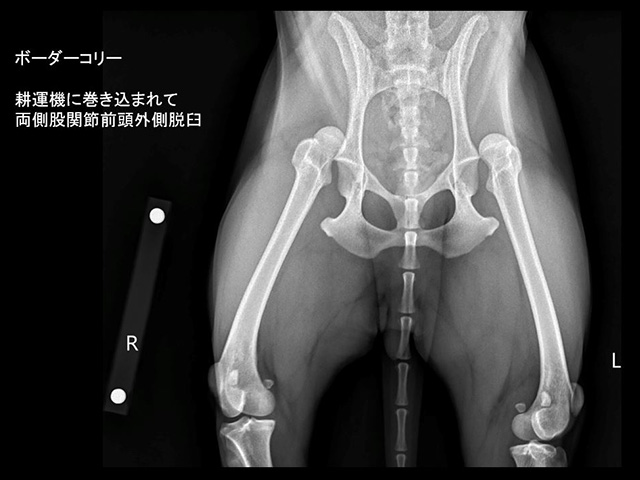

股関節脱臼Hip Dislocation

股関節脱臼は、転倒や同居犬との騒擾、着地失敗、交通事故などが原因で、股関節への強い剪断力が加わったことで生じます。